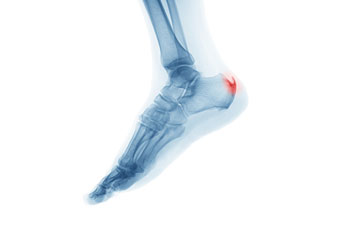

A heel spur takes the form of a bony-like growth. This is due to a calcium deposit that extends between the heel bone and foot arch. They can grow up to half an inch in length; however, they may not be outwardly visible. Because heel spurs tend to grow, increasing the overall discomfort felt, it’s important that you seek professional help as soon as pain is experienced for early detection.